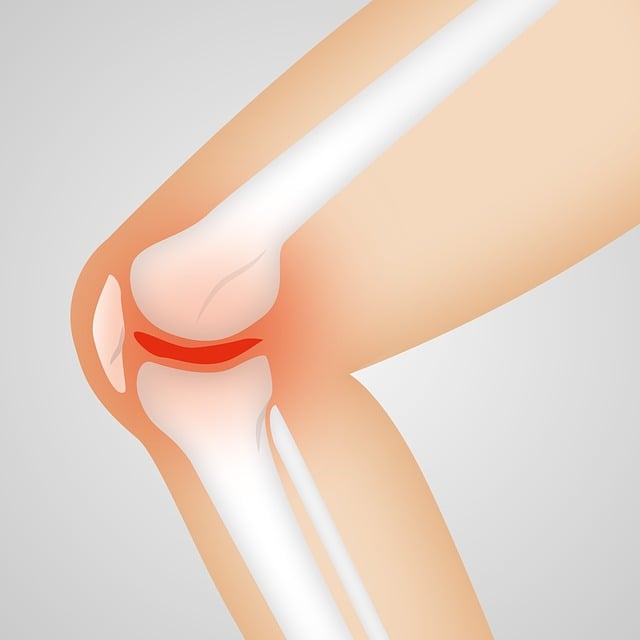

류마티스 관절염은 면역계가 자신의 관절을 공격하는 만성 염증성 질환입니다. 주로 손과 발의 작은 관절부터 시작해 전신으로 퍼질 수 있으며, 조기에 발견하고 치료하는 것이 중요합니다. 단순한 노화로 인한 관절염과는 달리 면역계 이상으로 발생하는 자가면역질환이라는 점에서 차이가 있습니다.

손목과 손가락 관절이 붓고 열감이 느껴지며 눌렀을 때 통증이 있다면 염증이 진행 중일 가능성이 큽니다. 보통 양쪽 관절에 대칭적으로 증상이 나타나는 것이 특징입니다.